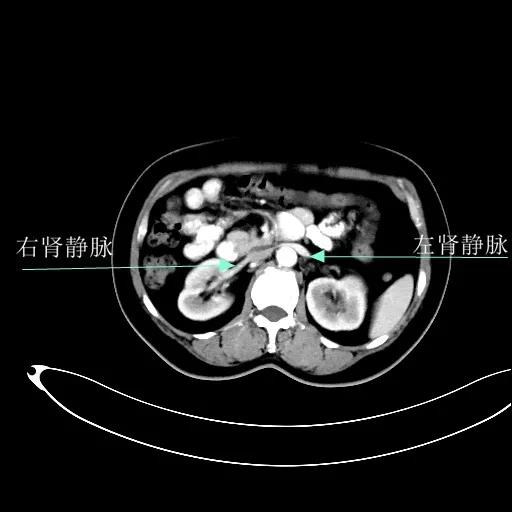

某患者因为“腹痛1周”而入院,外院B超提示子宫上方囊实性肿物,CT提示:左侧附件区占位,并盆腔及腹主动脉旁淋巴结转移。右肾动脉有右肾动脉及异位右肾动脉,其下均有肿大淋巴结。

排除禁忌后,在全麻下行“次广泛子宫切除+双附件切除+大网膜切除+阑尾切除术+盆腔淋巴结及腹主动脉旁淋巴结切除术”。术中切除腹主动脉左旁、右旁及后方淋巴结,达左右肾动静脉水平。多个淋巴结呈融合状态,长径约3-5cm。手术由陈亮副主任医师和宋趣清主治医师完成。

妇科一病区严格遵循指南推荐,在影像学或探查淋巴结阳性的晚期卵巢癌中,若能达到满意减瘤,仍常规行盆腔及腹主动脉旁肿大淋巴结切除/清扫术(如下图举例)。通过前期初步统计分析,肠系膜下动脉至肾静脉下淋巴结转移阳性率为25%左右,在全部腹主动脉旁淋巴结转移患者中约占30%,显示了肾静脉下腹主动脉旁淋巴结清扫的价值。其对生存的影响有待进一步观察。